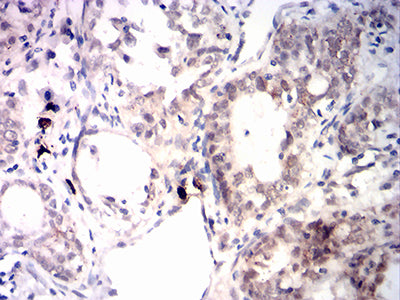

分类: 科研抗体货号: 31876别名: FCC2; COCA2; HNPCC; hMLH1; HNPCC2应用: IHC,FCM反应种属: Human